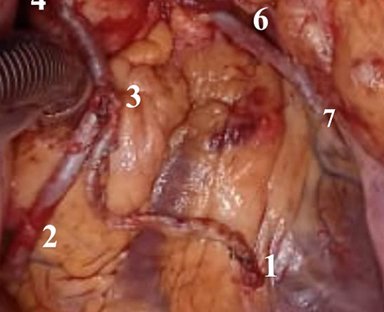

En esta sección se visualizarán cirugías reales en pacientes. Las fotografías por lo tanto

-si bien claras- en ocasiones privilegian la seguridad del paciente antes de

la exposición anatómica ideal.